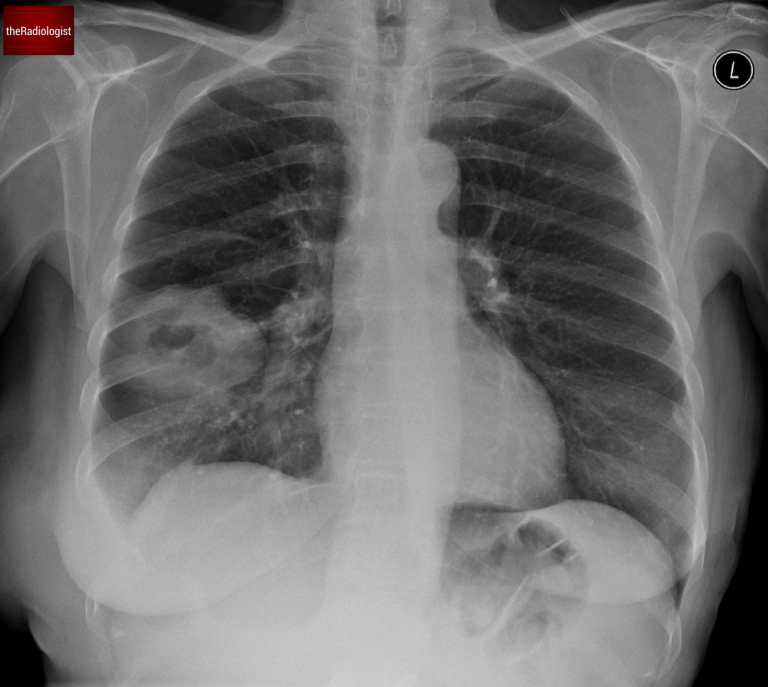

Unlike the previous case, there was no rib destruction. However, there was increased density within the right paratracheal region and an enlarged azygos contour.

This points towards right sided paratracheal lymph node enlargement. Bulky lymph nodes can point more towards cancer however mild node enlargement can be seen in both infections and cancer.

Look at the right paratracheal region: we have loss of the right paratracheal stripe and there is increased density in this region suggesting nodal enlargement.

A CT scan provided further clarity:

• The lesion’s wall thickness was measured at less than 2 cm.

• Surrounding ground-glass opacity and consolidation were noted.

• The right paratracheal lymph node enlargement seen on X-ray was confirmed.

The wall of the cavitating lesion measures at less than 2 cm and there is surrounding consolidation and groundglass opacity.

In this case, the wall thickness was less than 2.4 cm so we cannot say this is more likely cancer. The surrounding consolidation reinforced the likelihood of a benign cause.

To add to the evidence, the patient had raised inflammatory markers and symptoms of cough and fever. These pointed strongly toward an infective cause rather than malignancy.

The patient was treated with antibiotics, and a follow-up X-ray showed complete resolution of the lesion, confirming an infective etiology.

Follow up chest X-Ray at 2 months shows resolution of the right sided cavitating lesion.